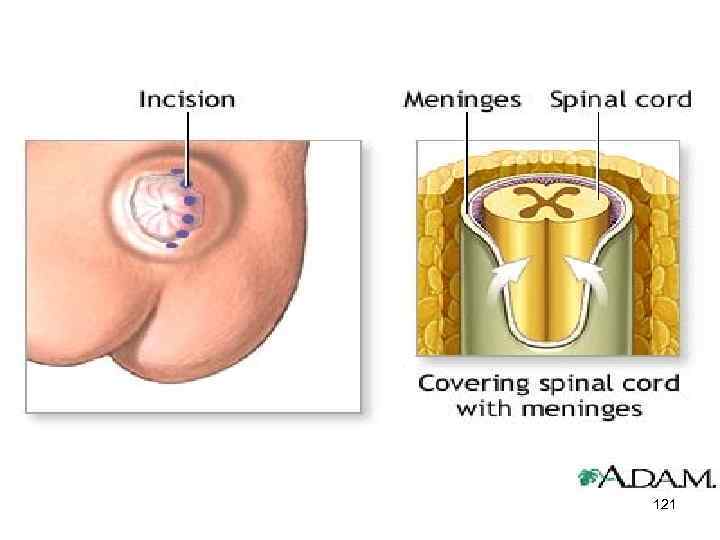

120

121